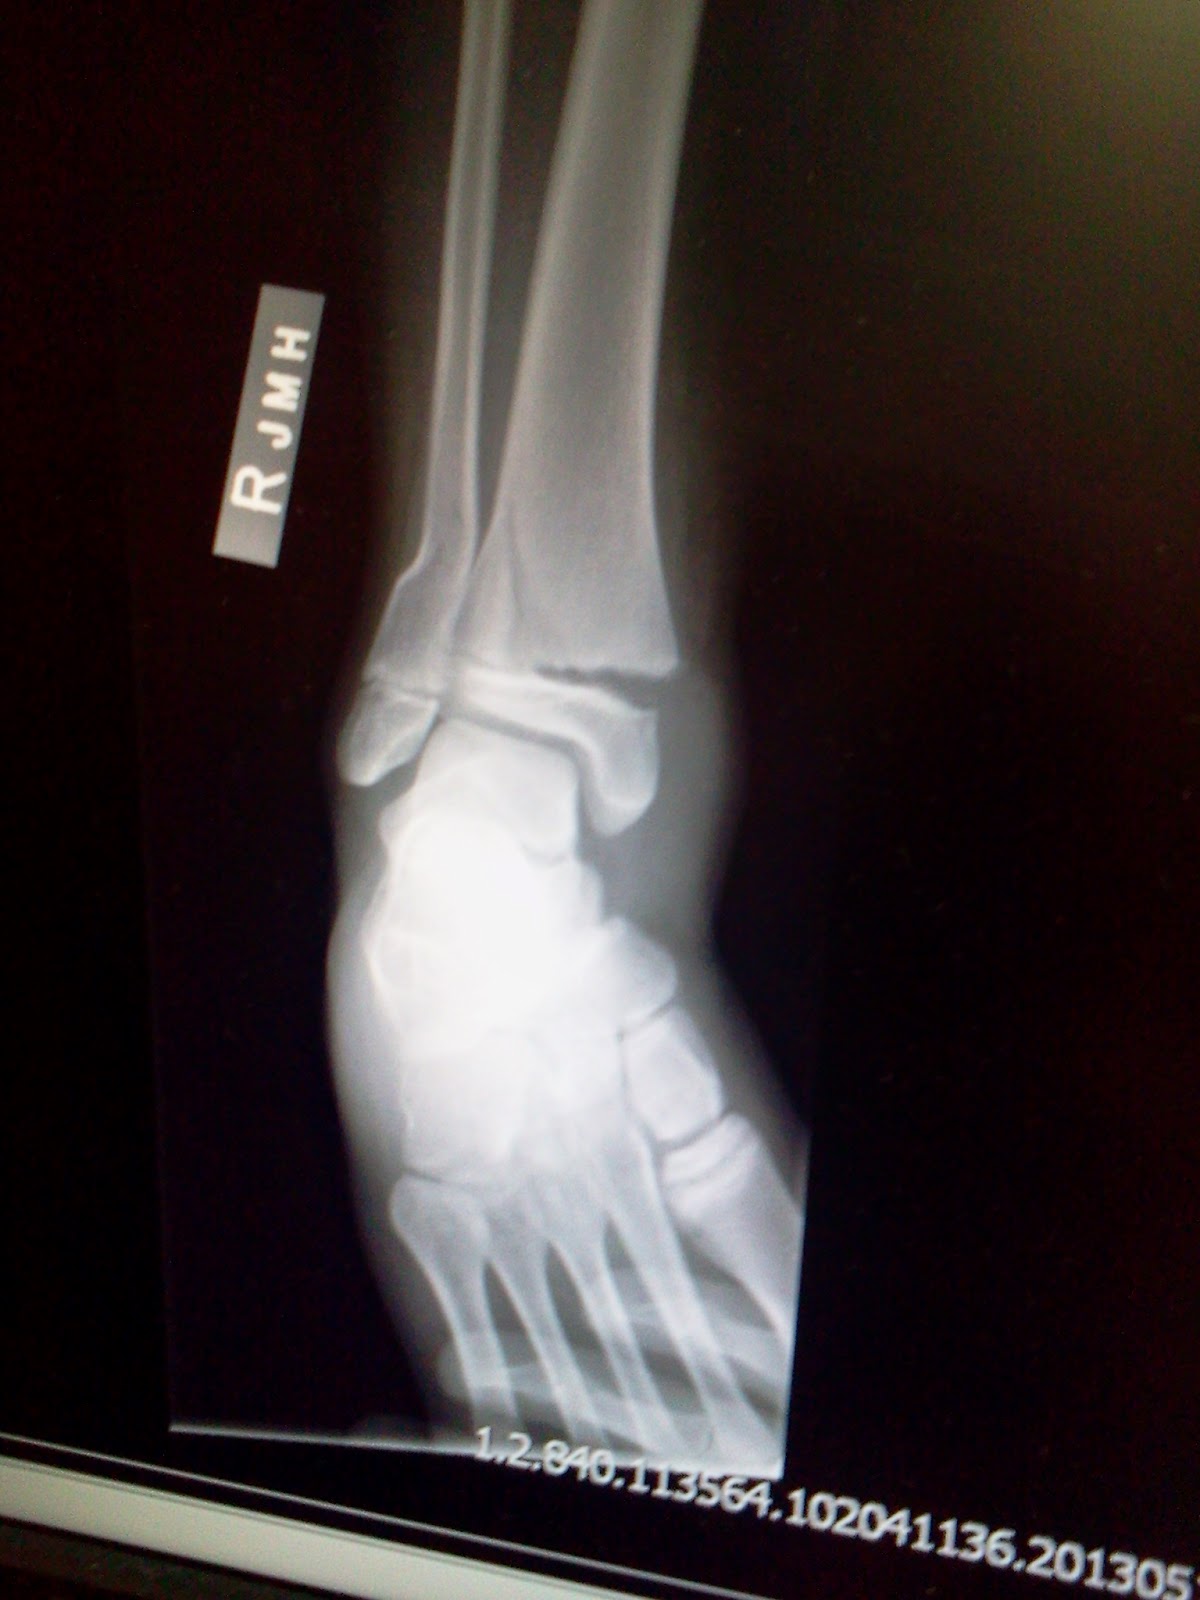

The sun was setting and the chill was starting to set in. The game was beginning to wind down, and John and I were talking about what to have for dinner. With only a few plays left in the game we knew we'd be going home soon to hungry kids. Just then, as Kaitlyn was playing the position of catcher, a girl from the other team slid into home. As she slid, she caught Kaitlyn's ankle, and Kaitlyn went down fast, and the teams took a knee. I went out to the field quickly. Right away I could tell things weren't good. Kaitlyn has always been a fighter. Never shows any sign of pain or sign of weakness, especially not in front of others, and really never in front of her team. But here she was, laying in the dirt as her coaches were trying to console her and determine the extent of her injuries. The look of fear and pain in her eyes were all I needed to know that this night was going to be a long one. We assessed things a bit more in the dugout before we hauled her out in a wagon. John stayed with us as I drove her to the E.R., I've never seen her in so much pain. She was pale, and shock was starting to set in as she shivered. A few x-rays were done, but it doesn't take an expert to see that it was broken, and broken bad. Both the femur and the tibia had been broken. And even better was that it had been done in the growth plate.